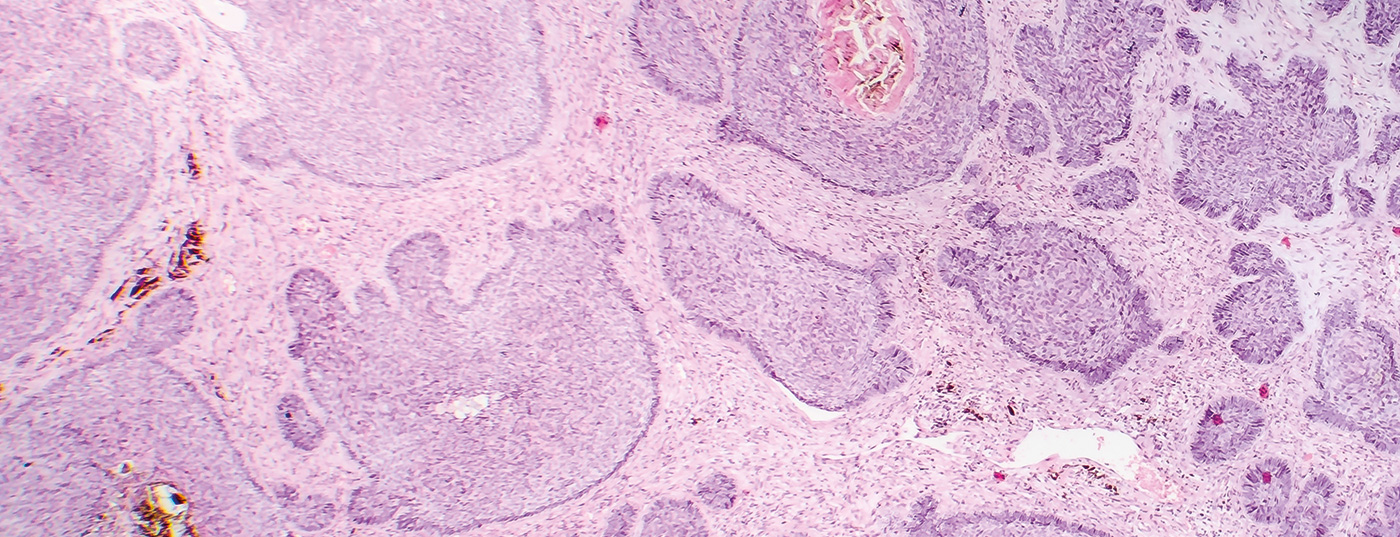

KI-basierte Algorithmen haben das Potenzial, die dermatopathologische Diagnoseerstellung in Zukunft zu unterstützen. Aktuell sind viele diesbezügliche Forschungsbemühungen im Gange. Unter anderem wurde ein Deep Learning-Algorithmus entwickelt, welcher für die Detektion von Basalzellkarzinomen und Plattenepithelkarzinomen genutzt werden kann. Das Ziel ist eine rasche und akkurate KI-gestützte Beurteilung.